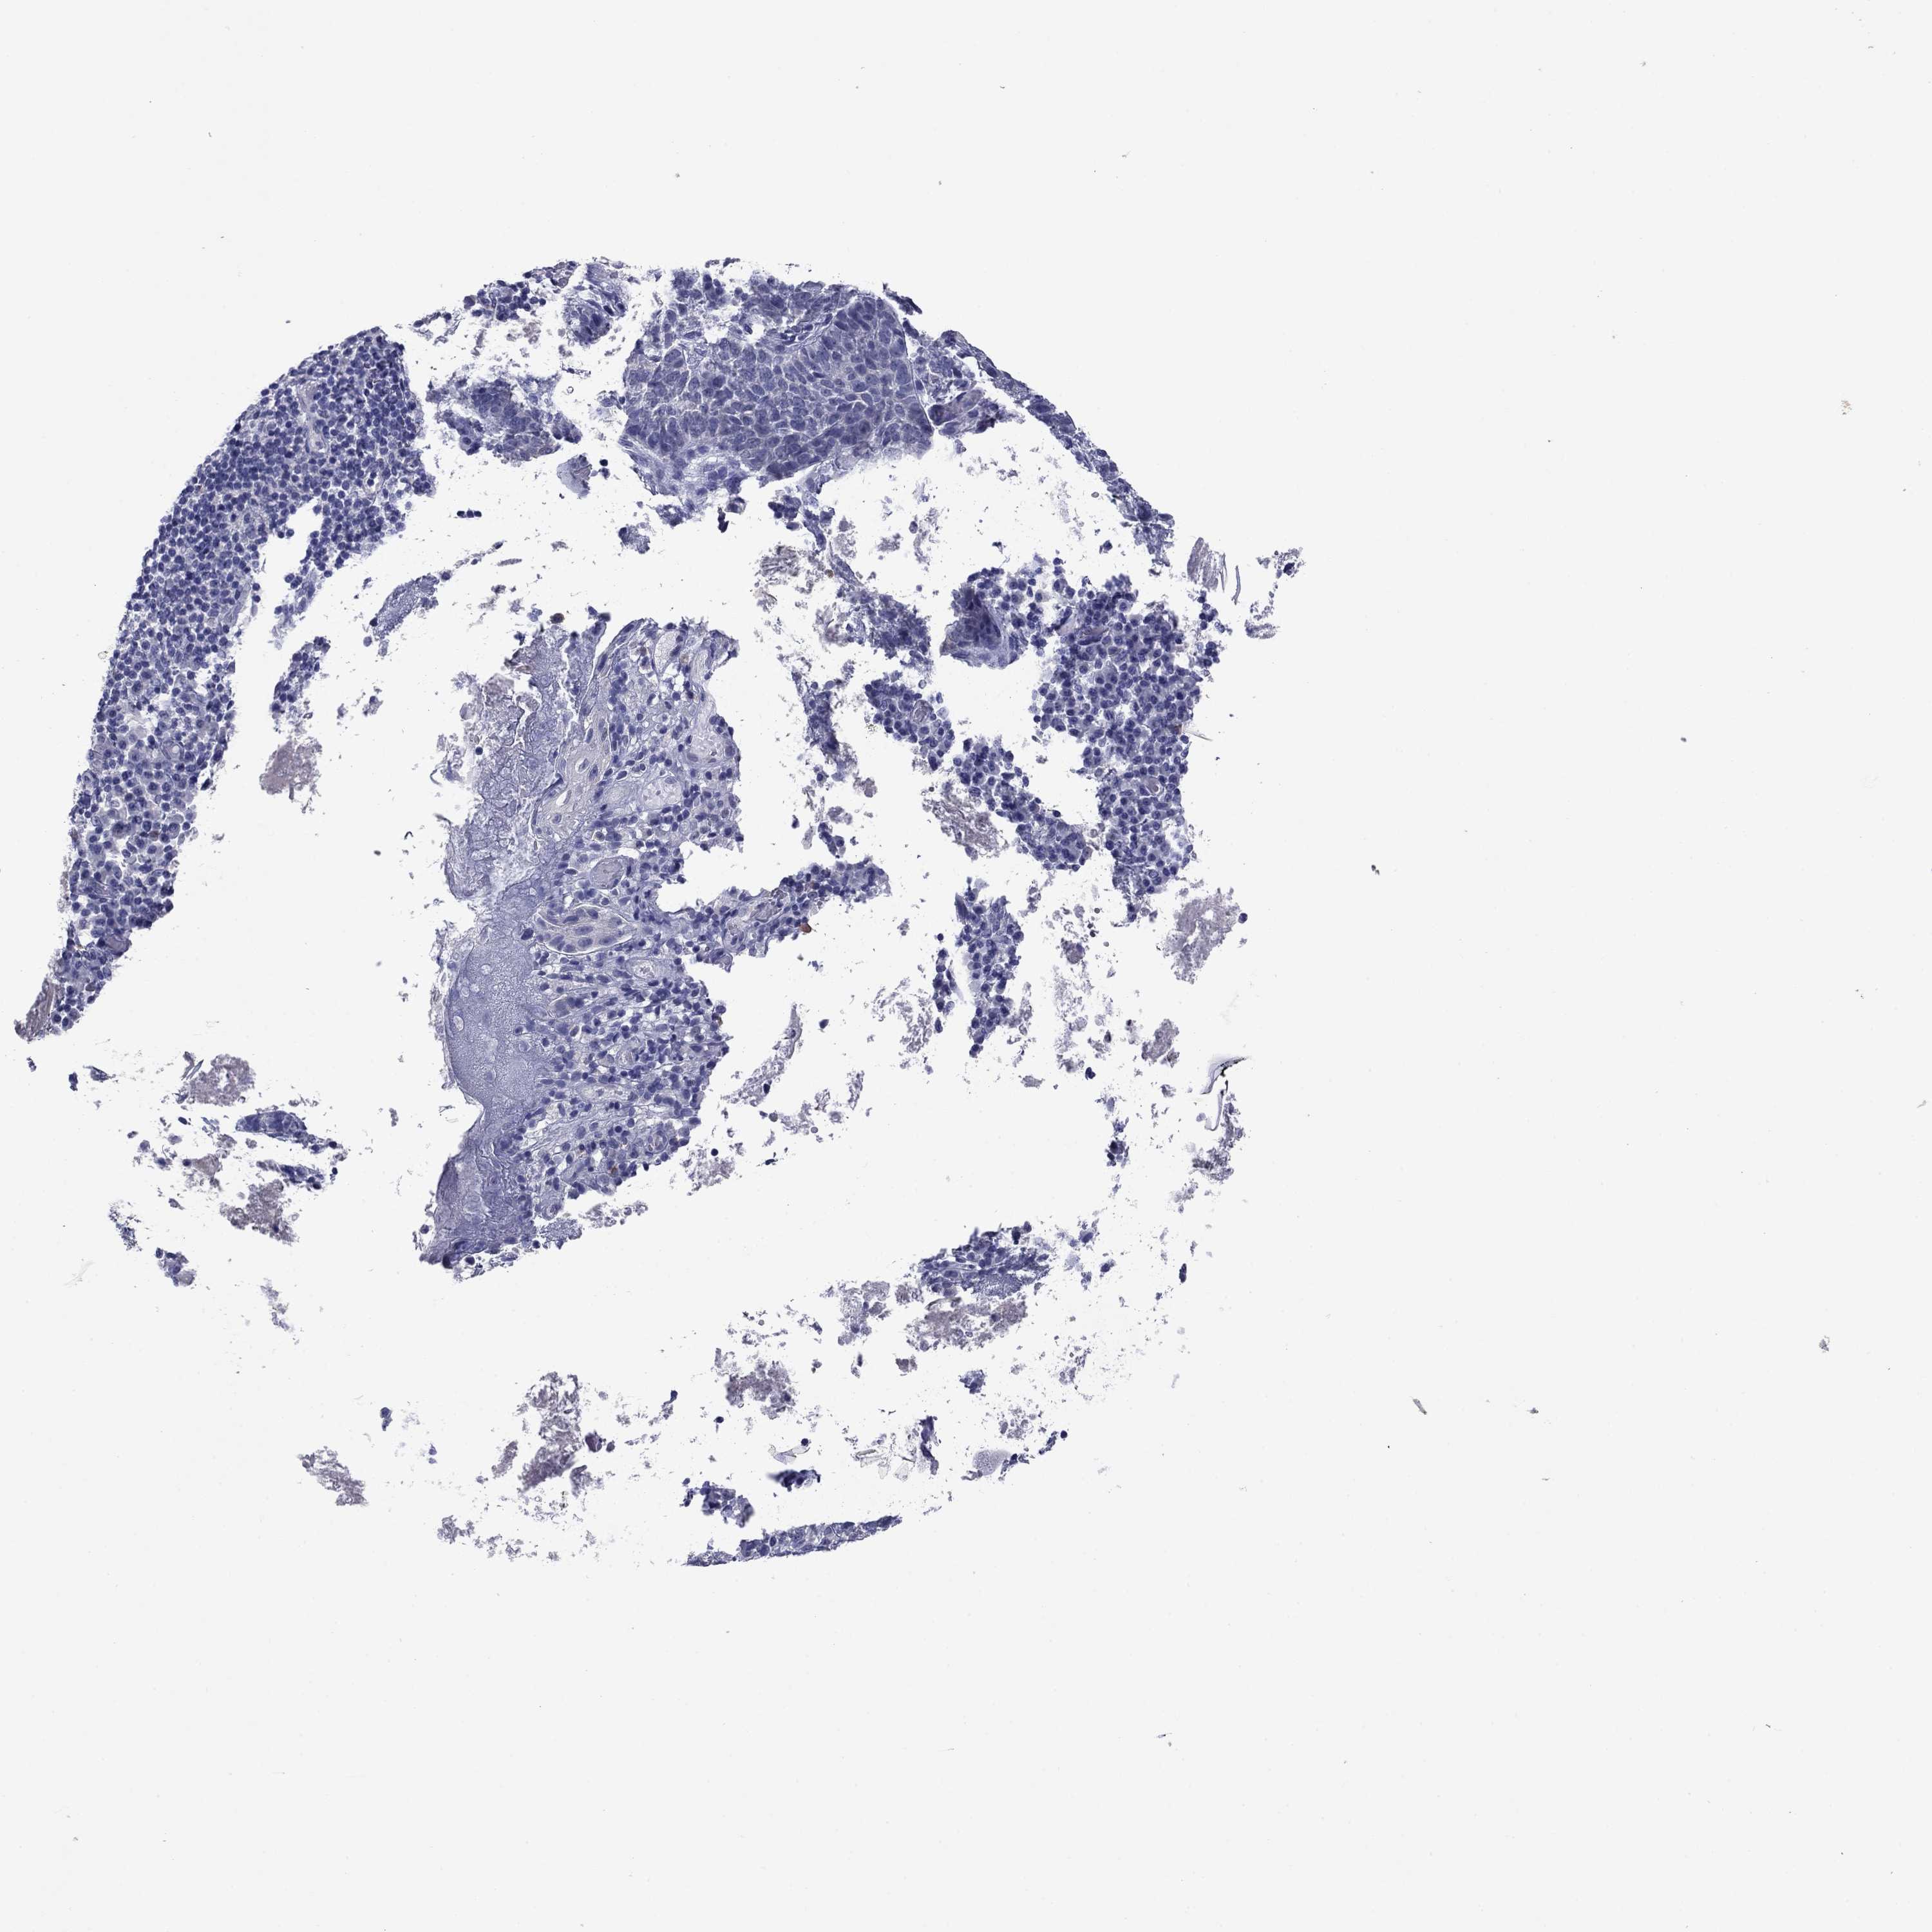

Basal cell and squamous cell cancer

SKIN CANCER - Protein expressioni

A mouse-over function shows sample information and annotation data. Click on an image to view it in a full screen mode. Samples can be filtered based on level of antibody staining by selecting one or several of the following categories: high, medium, low and not detected. The assay and annotation is described here.

Antibody stainingi

Antibody staining in the annotated cell types in the current human tissue is reported as not detected, low, medium, or high, based on conventional immunohistochemistry profiling in selected tissues. This score is based on the combination of the staining intensity and fraction of stained cells.

Each image is clickable and will lead to virtual microscopy that enables deeper exploration of all samples and also displays staining intensity scores, fraction scores and subcellular localization as well as patient and tissue information for each sample.

Antibody HPA049552

Antibody HPA072442

Staining

High

Medium

Low

Not detected

Intensity

Strong

Moderate

Weak

Negative

Quantity

>75%

75%-25%

<25%

None

Location

Nuclear

Cytoplasmic/membranous

Cytoplasmic/membranous,nuclear

Basal cell carcinoma

Squamous cell carcinoma, NOS

Squamous cell carcinoma, metastatic, NOS